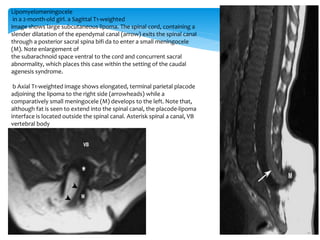

in a 2-month-old girl. a Sagittal T1-weighted

image shows large subcutaneous lipoma. The spinal cord, containing a

slender dilatation of the ependymal canal (arrow) exits the spinal canal

through a posterior sacral spina bifi da to enter a small meningocele

(M). Note enlargement of

the subarachnoid space ventral to the cord and concurrent sacral

abnormality, which places this case within the setting of the caudal

agenesis syndrome.

b Axial T1-weighted image shows elongated, terminal parietal placode

adjoining the lipoma to the right side (arrowheads) while a

comparatively small meningocele (M) develops to the left. Note that,

although fat is seen to extend into the spinal canal, the placode-lipoma

interface is located outside the spinal canal. Asterisk spinal a canal, VB

vertebral body